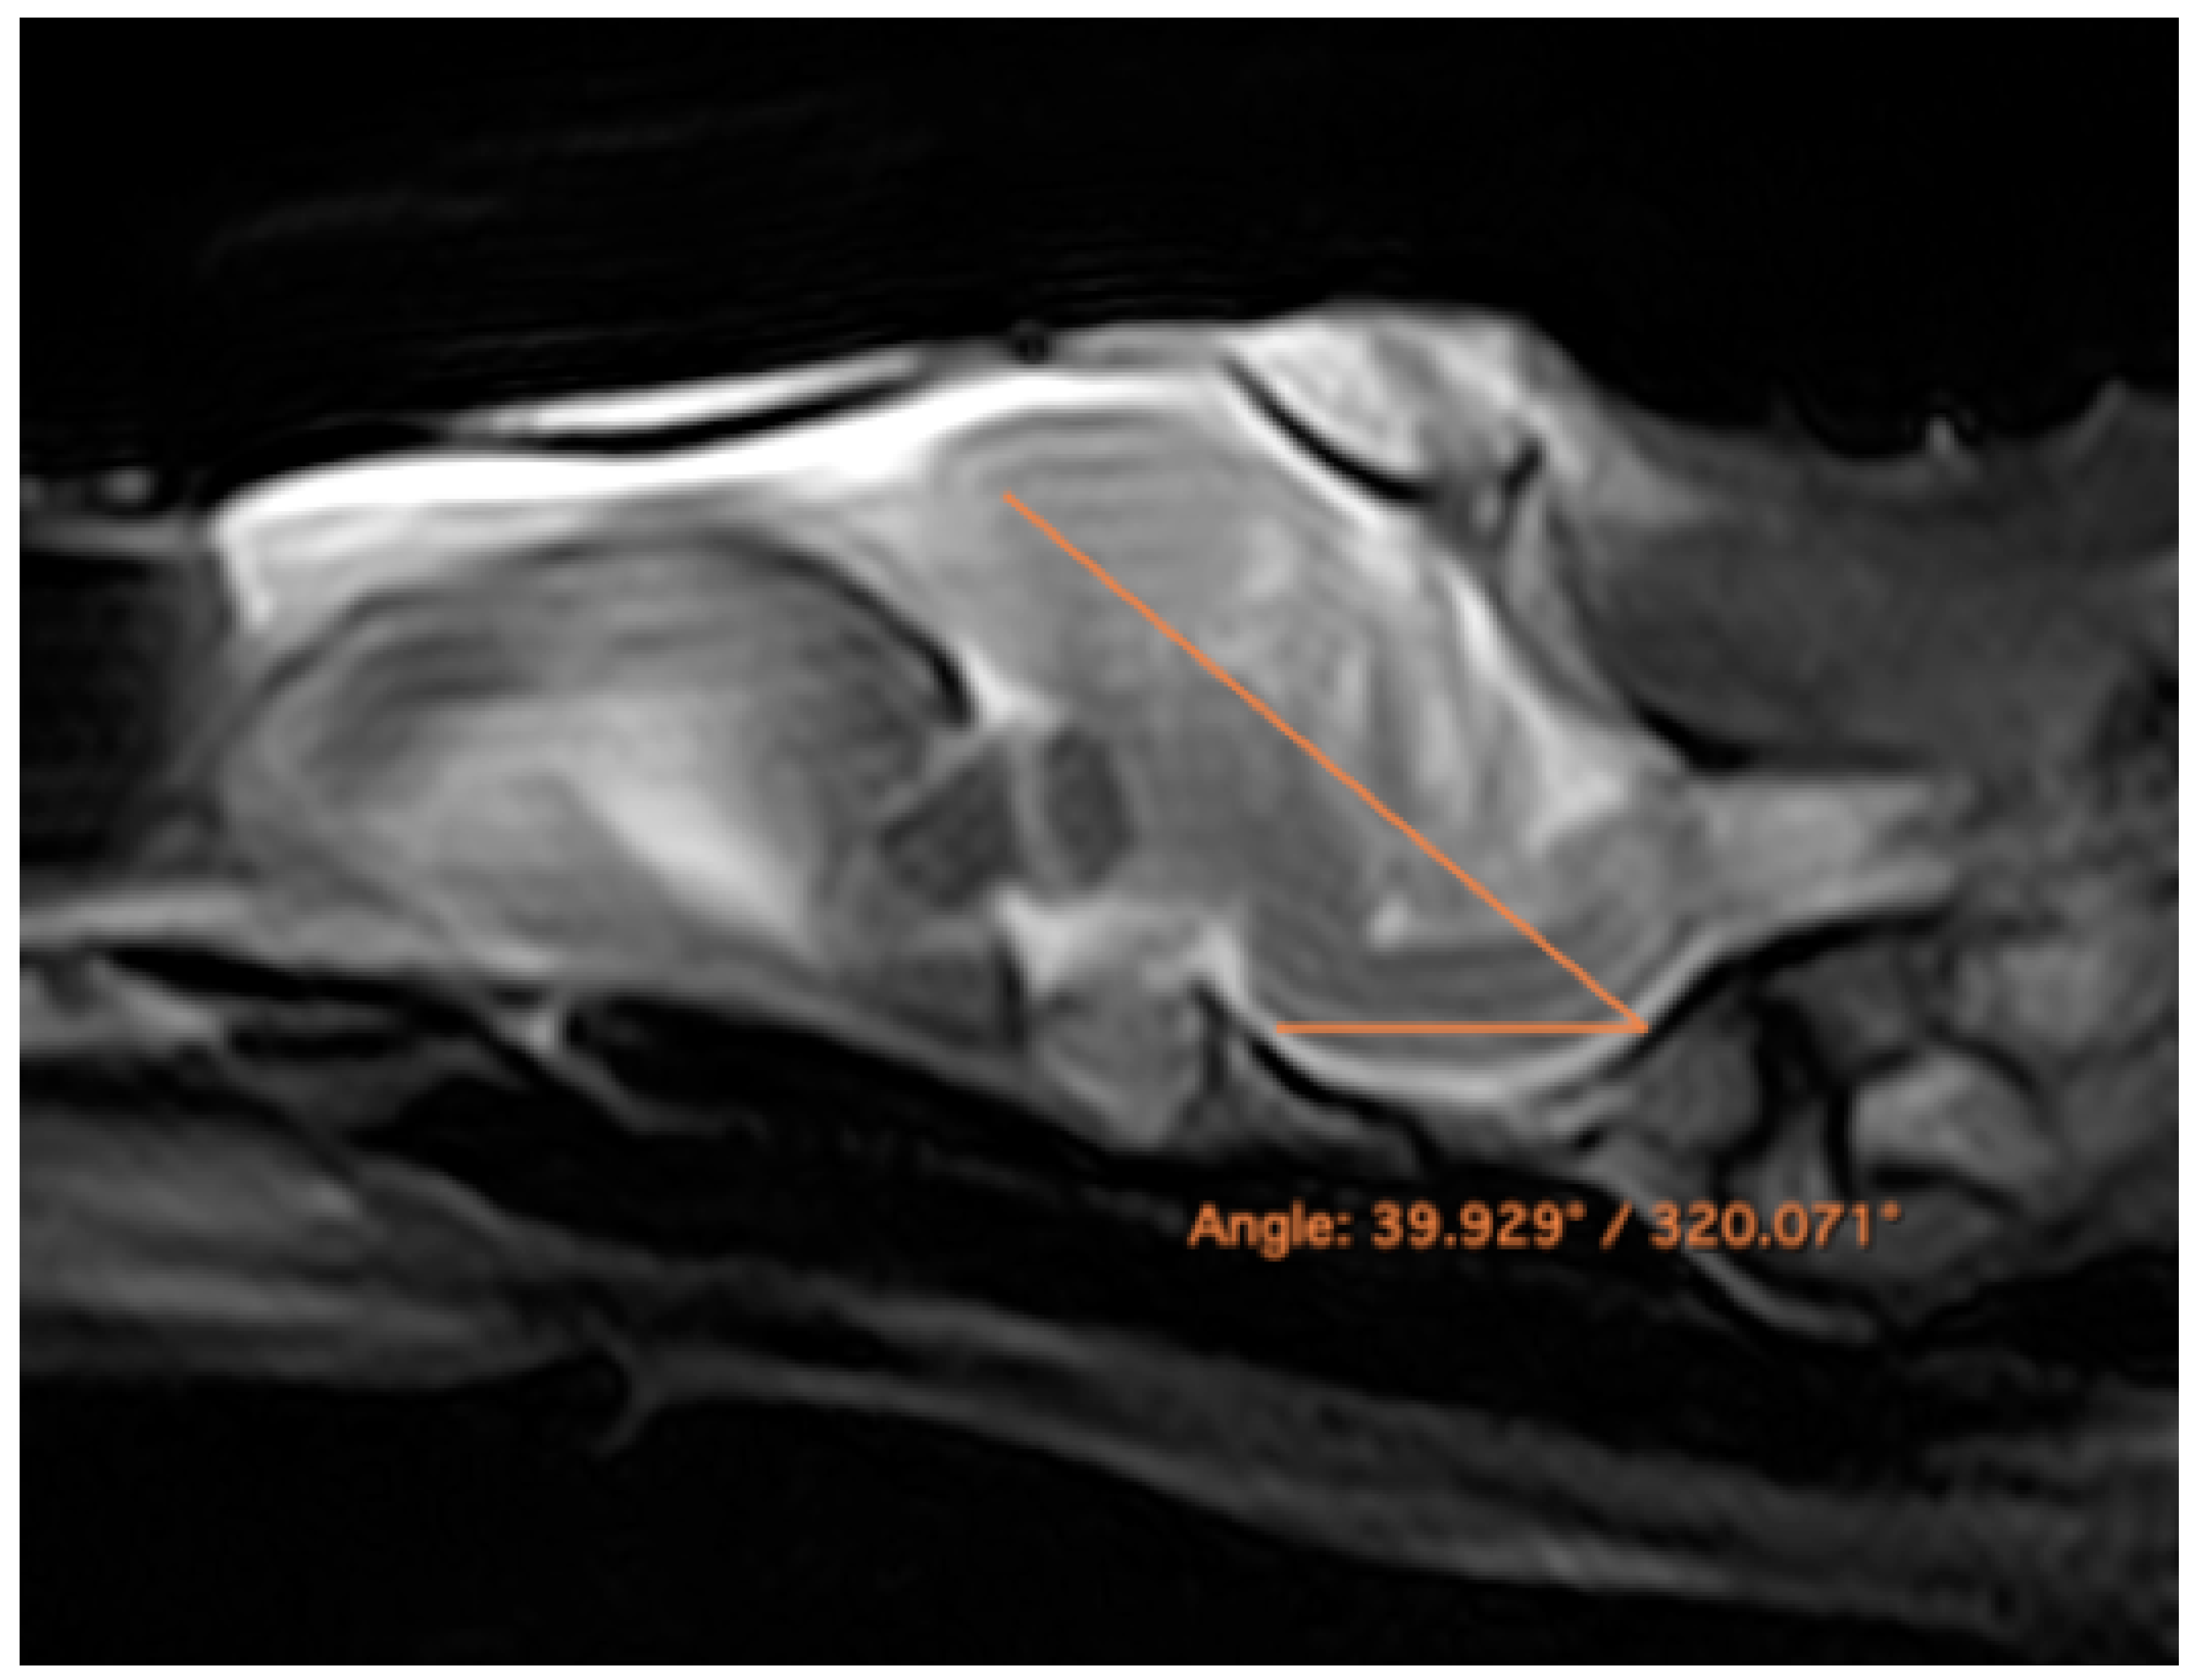

3.3. Magnetic Resonance Imaging (MRI)